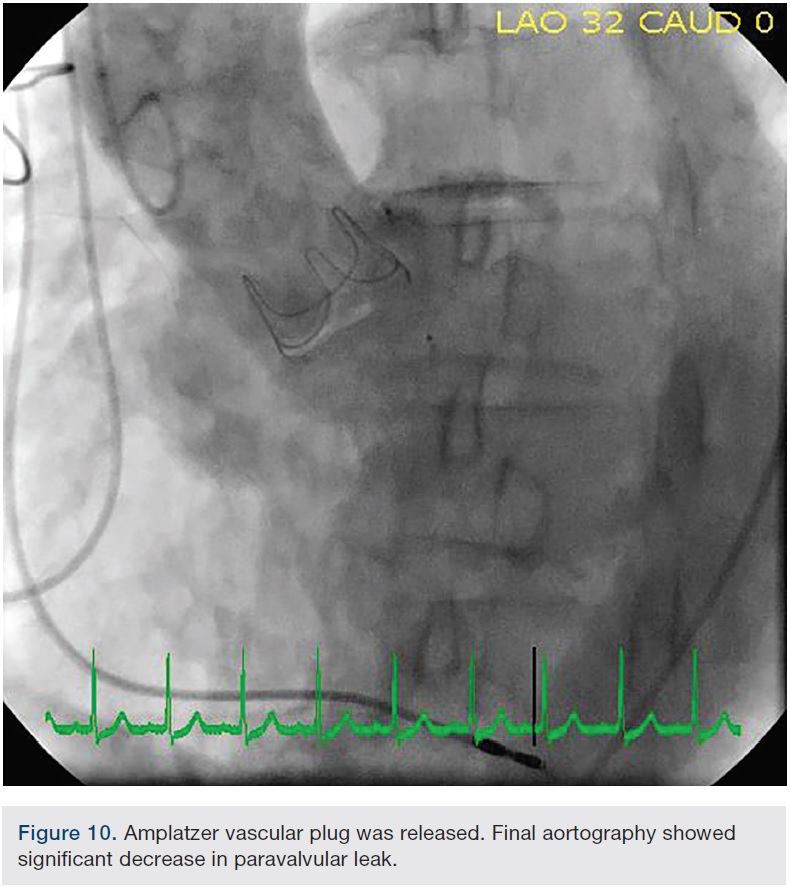

At this point, the approach was changed. The Extra Back-Up (EBU) 3.5 guide was advanced from the femoral approach to selectively engage the left main ostium. The EBU guide was left in place to protect the left main ostia, because the paravalvular leak was closed to the left main origin. Using a 5 French JR4 guide catheter via the right radial access, we were able to successfully advance the JR4 guide catheter through the paravalvular leak (Figure 5). A 5 French, 90cm Destination sheath was telescoped over the 5 French guide catheter across the PVL. Under TEE and fluoroscopic guidance, an 8mm Amplatzer Vascular Plug (St. Jude Medical) was deployed across the PVL and through the Destination sheath, and a tug test was performed. (Figure 6A-B, 7). The final TEE imaging showed a well-deployed Amplatzer Vascular Plug into the paravalvular aortic annular defect, with a significant decrease in paravalvular regurgitation compared with the pre-procedure study (Figures 8, 9). A trace to mild paravalvular insufficiency and a mild intrinsic central aortic insufficiency were seen (Figure 10). A hemostatic band and a vascular closure device were used to achieve hemostasis in the radial artery and femoral artery, respectively. The patient tolerated the procedure well and she was discharged from the hospital the next morning. At her follow-up visit, she had significant improvement in her symptoms.